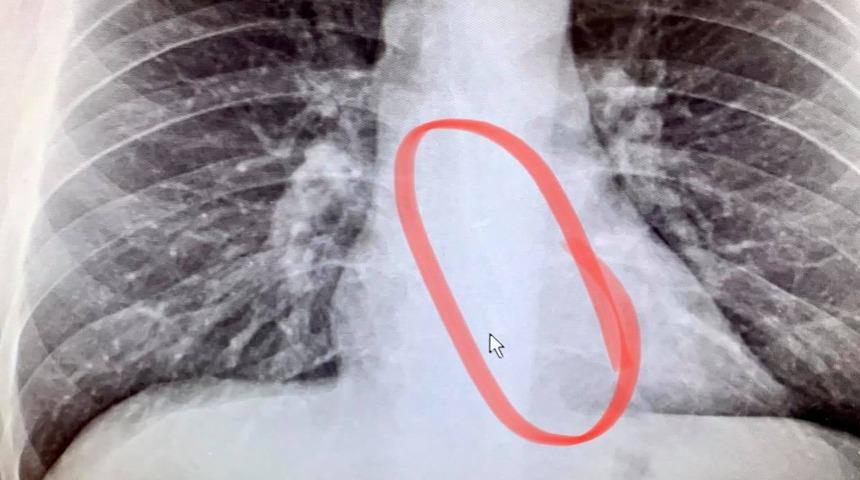

Acil servise başvuran ABD'li adam, hastaneye gittiğinde gerçeği öğrendi. Gauthier'ın aklını kemiren düşünce doğru çıktı. Hastanede çektirdiği röntgen filminde Gauthier, kaybolan kulaklığın tekini yemek borusunda buldu. Yemek borusundaki kulaklık, hemen endoskopi ile Gauthier'ın yemek borusundan çıkartıldı.